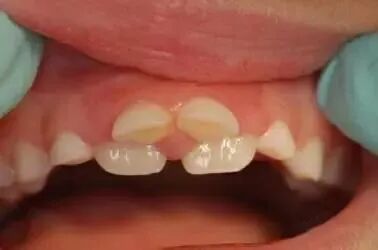

曲面断层片怎么看换牙与身高有关吗?关于孩子换牙的所有疑问一篇说清_https://www.jmylbn.com_新闻资讯_第15张

曲面断层片怎么看换牙与身高有关吗?关于孩子换牙的所有疑问一篇说清_https://www.jmylbn.com_新闻资讯_第16张

图注:左图:乳前牙有缝,右图:乳前牙没缝

3. 上颌“双排牙”应尽早拔除,避免造成“地包天”。